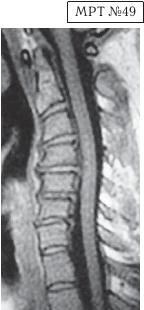

На МРТ № 47 наблюдается сглаженность лордоза с незначительной кифотизацией, которая привела к абсолютному стенозу спинномозгового канала и блоку ликворных путей, а также протрузии в сегменте СIV-СV, вентральному спондилёзу в сегменте CV-CVI и остеофитозу в сегменте CVI-CVII, гипертрофии передней и задней продольных связок. Это наиболее значительные проблемы в данном отделе. ![]() На МРТ № 48 наблюдается сглаженность лордоза, но без кифотической деформации, снижение высоты межпозвонковых дисков, протрузии в сегментах CV-CVI и CVI-CVII, частично компенсированные спондилёзом, выражены краевые остеофиты на данном уровне, абсолютный стеноз и блок ликворных путей, гипертрофия передней и задней продольных связок. ![]() На МРТ № 49 наблюдается кифоз шейного отдела позвоночника, хотя он и не привёл к абсолютному стенозу спинномозгового канала позвоночника, однако значительно нарушил ликвородинамику. Вентральное эпидуральное пространство блокировано вершиной кифоза с экскавацией и оттеснением спинного мозга, а дорсальное эпидуральное пространство блокируется чуть ниже от вершины задней стенкой спинномозгового канала. МРТ № 50